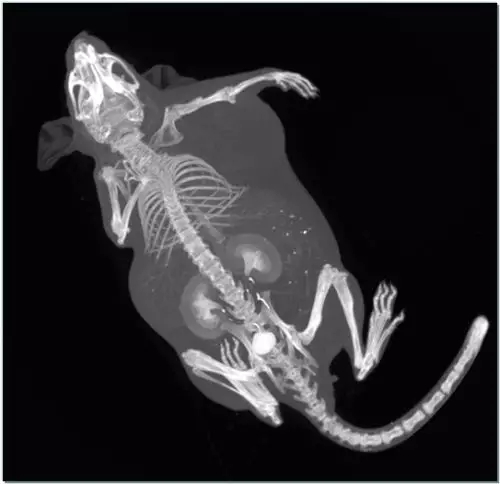

当然,我们研制的设备可不是专门用来扫描螃蟹有没有黄的,它真正的用途是临床前研究,用于小型动物活体的扫描,在不需要处死实验动物的情况下,可以对其全身或者任意感兴趣区进行最高10微米分辨的三维扫描。

来看看“小动物活体能谱CT”最近的应用成果。

应用二:肿瘤模型鼠全身扫描(碘对比剂)